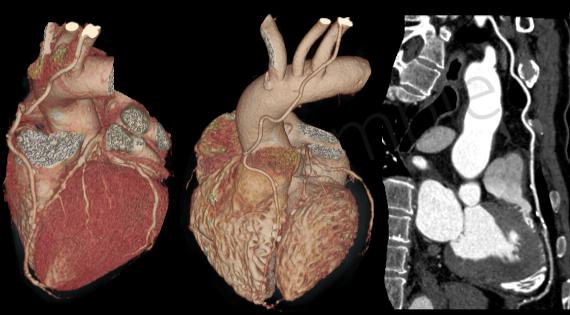

一、心血管疾病的诊断

由于该机扫描速度快、检测范围广,使整个心脏扫描可以控制在5秒内完成,实现了心血管疾病的无创早期诊断、心功能评价及术后疗效评价。在冠心病、先天性心脏病、心瓣膜病、心脏肿瘤的诊断发挥重要作用。

三、CT血管成像

CT血管造影(CTA,CT angiography)具有无创和操作简便的特点,对于心脏、头颈部、胸腹部甚至四肢的血管变异、血管疾病、血管狭窄、动脉瘤、主动脉夹层以及显示病变和血管关系有重要价值。